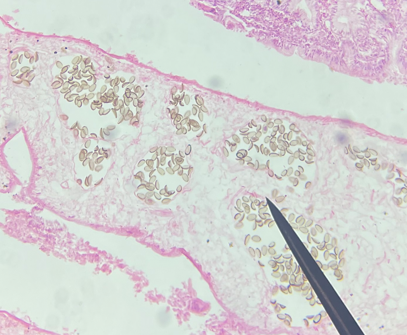

H&E stain of liver tissue

Trematode sporocyst

40X magnification

40X magnification